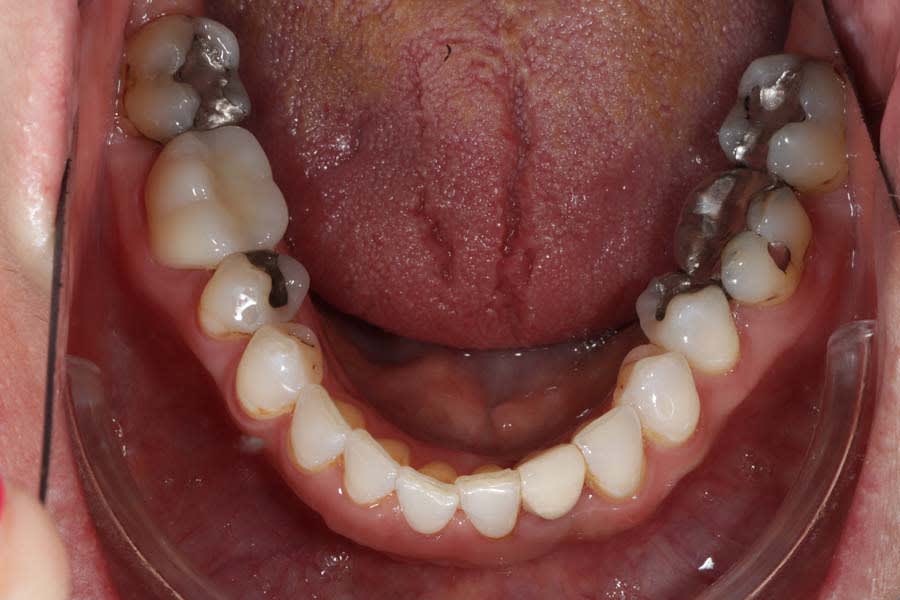

The patient expressed worry about further tooth fractures and dissatisfaction with anterior tooth wear and chipping (Figure 1 and Figure 2). She sought esthetic smile improvement and a comprehensive plan to prevent further breakdown and was open to a systematic approach to data gathering for diagnoses and planning. Historically reliant on single-tooth dentistry, she embraced a thorough approach that involved orthodontics and restorative care to address occlusal and esthetic issues.

Biomechanical: No active caries or xerostomia was noted, but the fractured amalgam on tooth No. 30 prompted urgent treatment. Large restorations on teeth Nos. 2, 3, 12 through 15, 18 through 20, and 31, along with large Class III composites on teeth Nos. 6 through 9, indicated structural compromises. Root canal treatment on teeth Nos. 4 and 10 (apicoectomy and post-and-core [FlexiPost®, Essential Dental Systems, edsdental.com]) and marginal fractures on teeth Nos. 5 and 12 put these teeth at even further risk. Despite the lack of symptoms, future pulpal pathology was a risk for many of the patient’s structurally compromised teeth (Figure 4 and Figure 5).